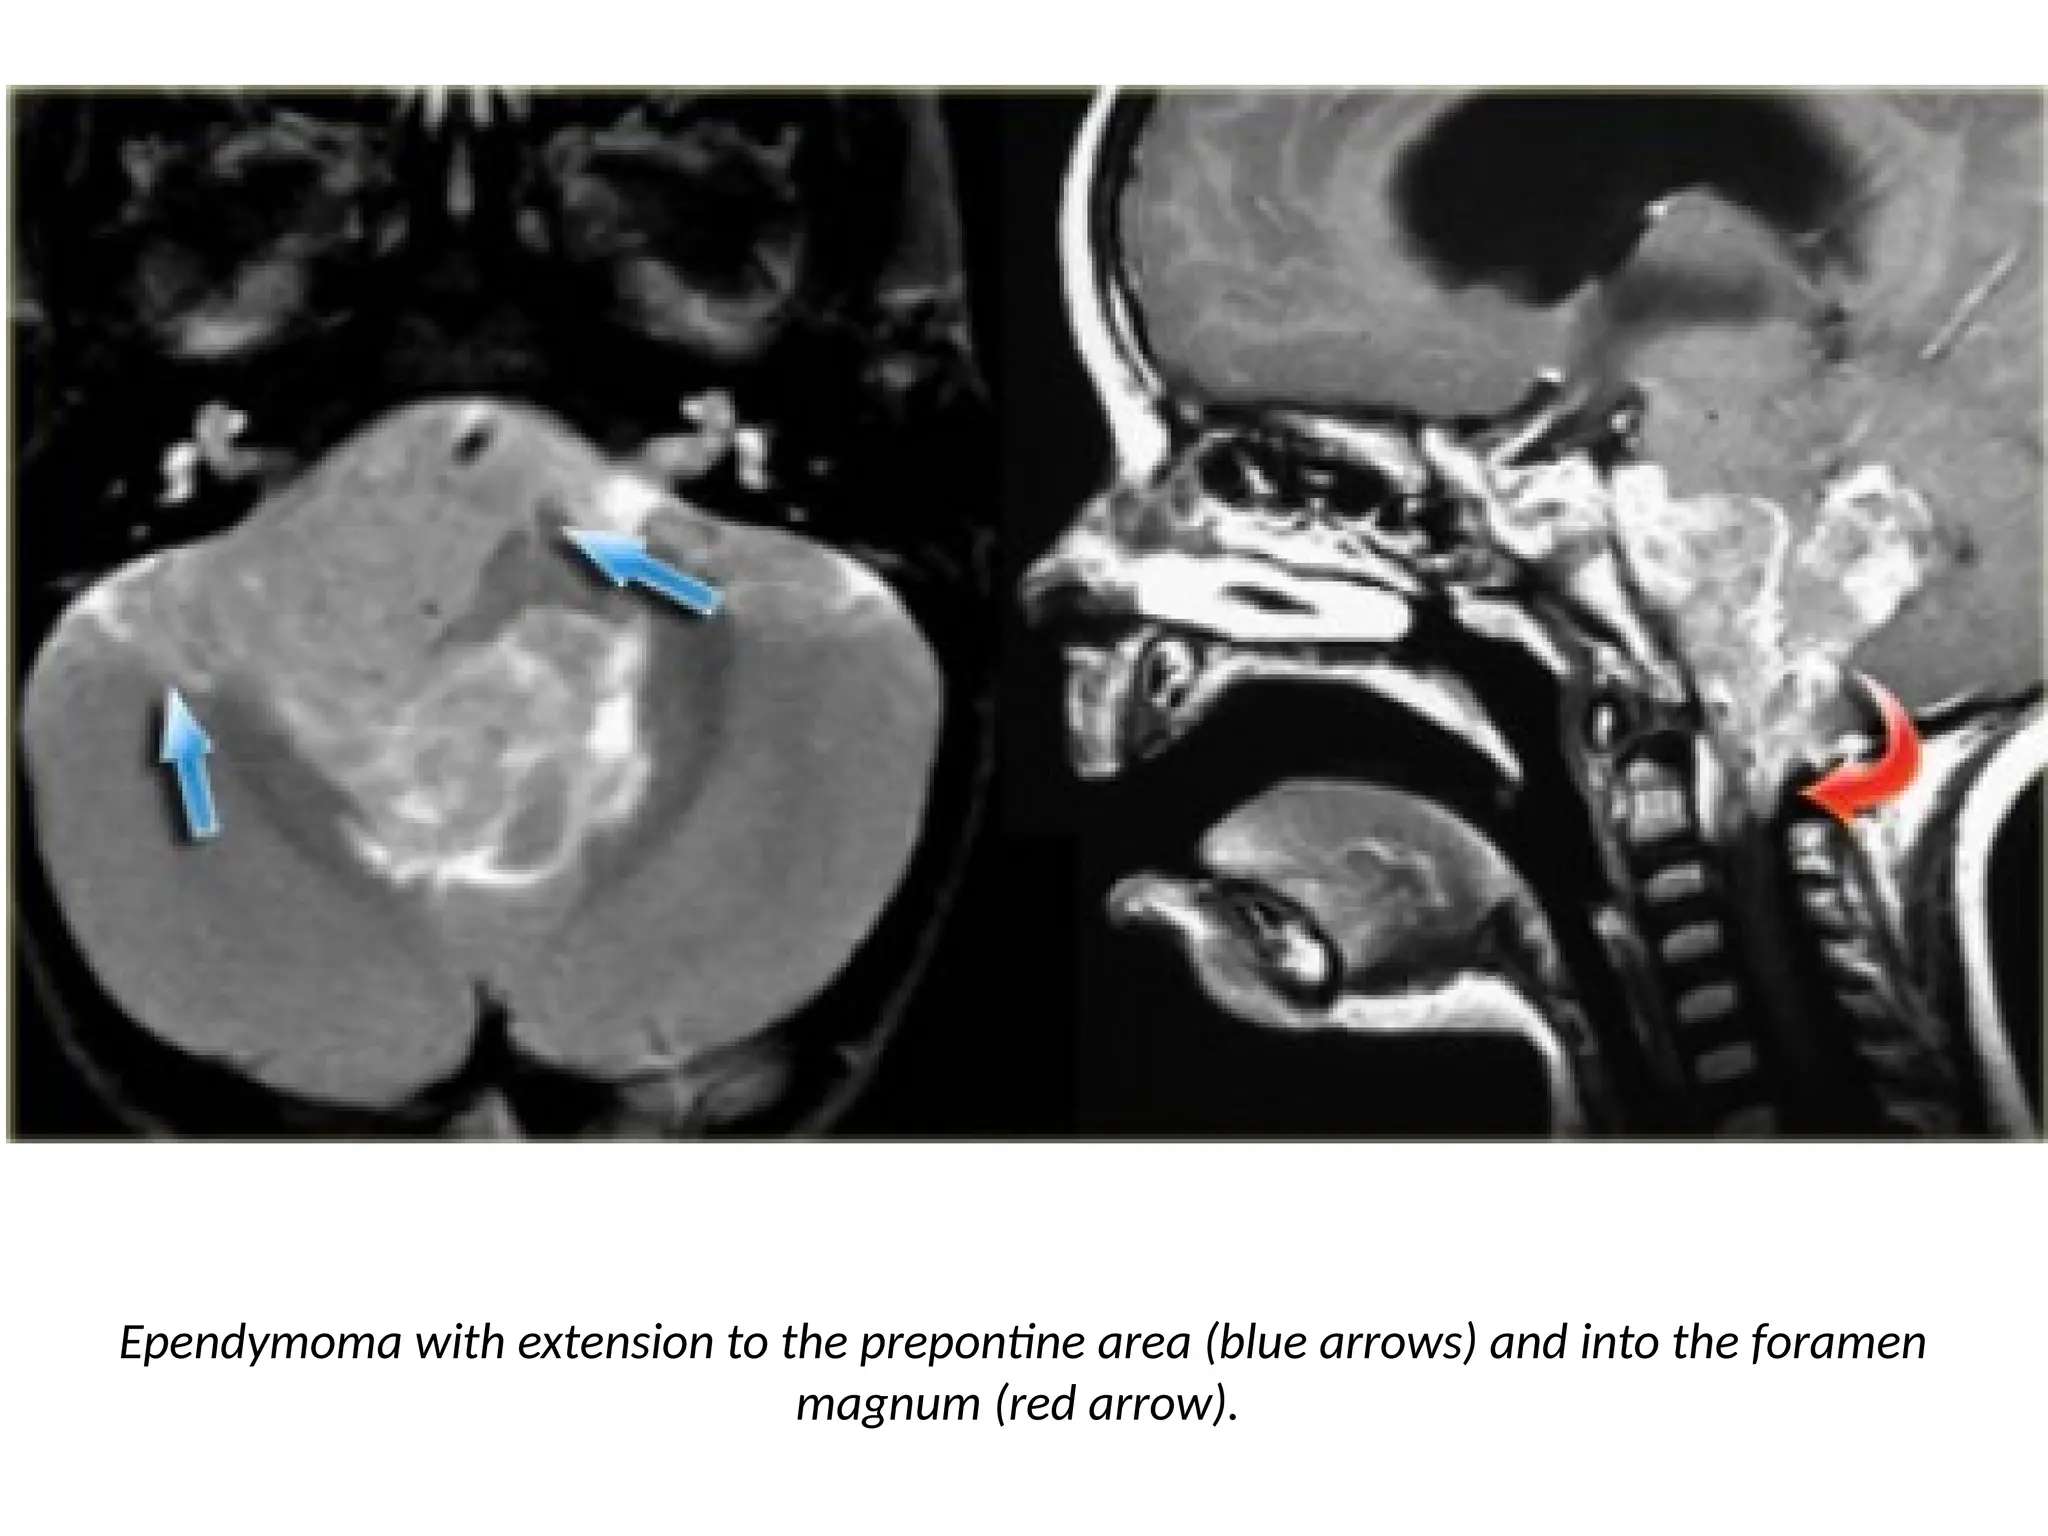

• Ependymomas of the fourth ventricle in children tend to

extend through the foramen of Magendie to the cisterna

magna and through the lateral foramina of Luschka to the

cerebellopontine angle.

Ependymoma with extension to the prepontine area (blue arrows) and into the foramen

magnum (red arrow).